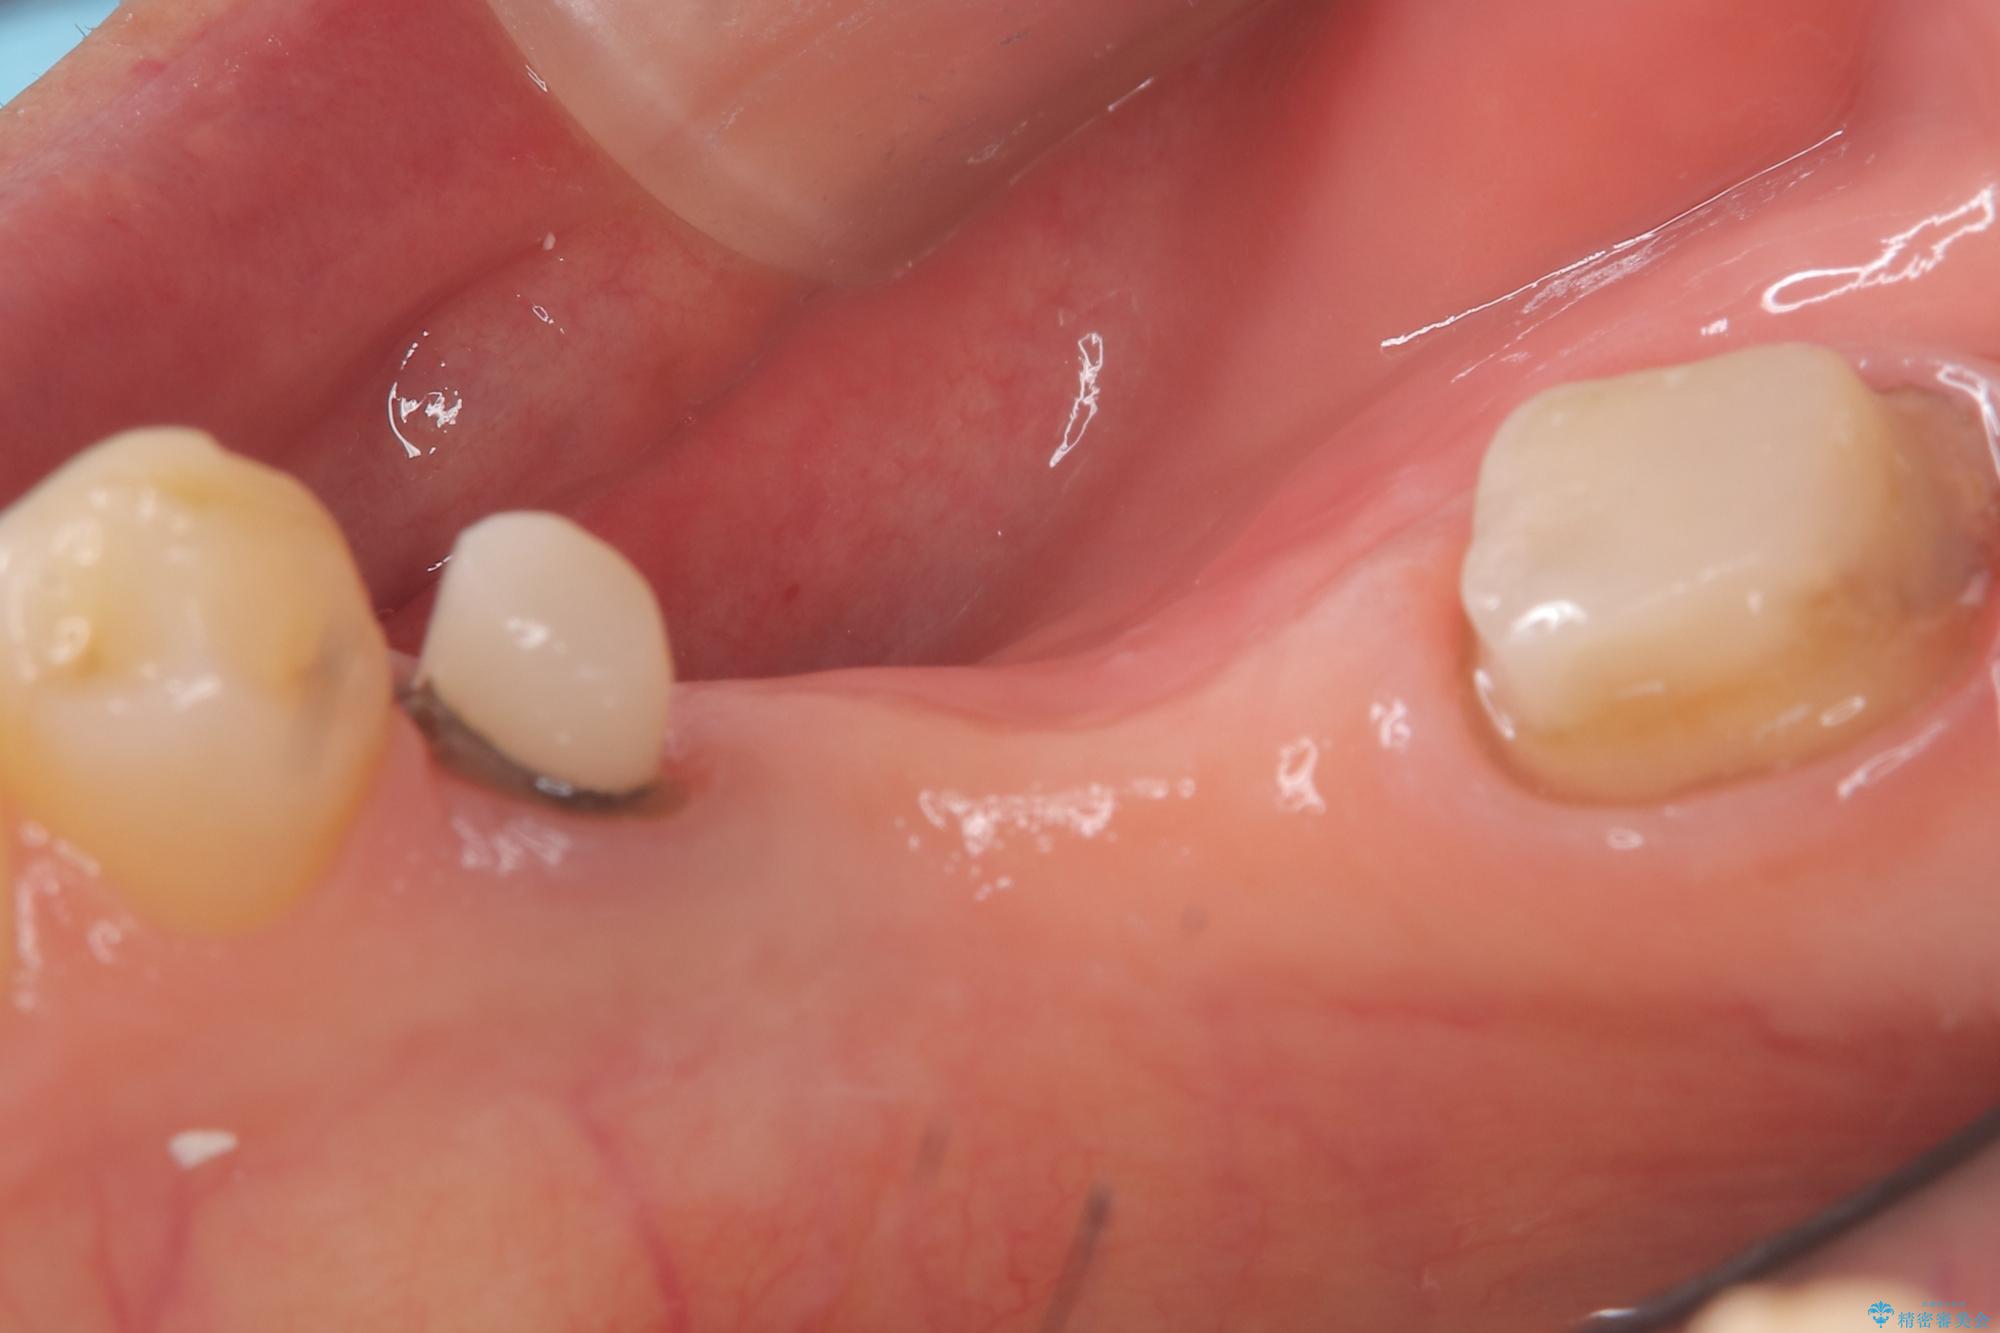

両支台歯が失活歯のため、どちらかもしくは両方の歯が破折した際、再度ブリッジを除去した治療が必要になるリスクとインプラント治療のご提案もさせていただきましたが、ブリッジでの治療を希望されました。

右下5番は支台歯CR築造を行っています。